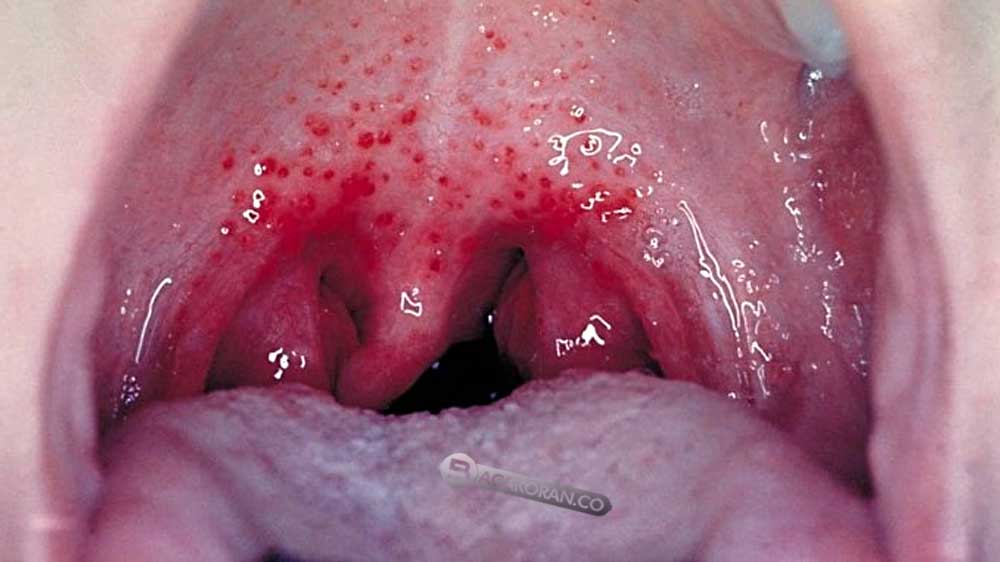

BACAKORAN.CO - Radang tenggorokan adalah kondisi yang umum dialami oleh banyak orang, terutama saat musim hujan atau pandemi.

Radang tenggorokan biasanya disebabkan oleh infeksi virus atau bakteri yang menyerang lapisan mukosa faring (tenggorokan) atau tonsil (amandel).

Gejala radang tenggorokan yang sering dirasakan antara lain sakit atau nyeri saat menelan, suara serak, batuk, demam, bercak putih pada tenggorokan atau amandel, pembengkakan kelenjar di leher, sakit kepala, dan nyeri perut.